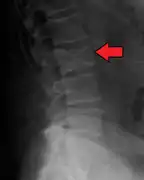

Bone pain

Illustration showing the most common site of bone lesions in vertebrae

Bone pain affects almost 70% of people with multiple myeloma and is one of the most common symptoms.[2]:653[22] Myeloma bone pain usually involves the spine and ribs, and worsens with activity. Persistent, localized pain may indicate a pathological bone fracture. Involvement of the vertebrae may lead to spinal cord compression or kyphosis. Myeloma bone disease is due to the overexpression of receptor activator for nuclear factor κ B ligand (RANKL) by bone marrow stroma. RANKL activates osteoclasts, which resorb bone. The resultant bone lesions are lytic (cause breakdown) in nature, and are best seen in plain radiographs, which may show "punched-out" resorptive lesions (including the "raindrop" appearance of the skull on radiography). The breakdown of bone also leads to the release of calcium ions into the blood, leading to hypercalcemia and its associated symptoms.[23]

Medical imaging

The diagnostic examination of a person with suspected multiple myeloma typically includes a skeletal survey. This is a series of X-rays of the skull, axial skeleton, and proximal long bones. Myeloma activity sometimes appears as "lytic lesions" (with local disappearance of normal bone due to resorption) or as "punched-out lesions" on the skull X-ray ("raindrop skull"). Lesions may also be sclerotic, which is seen as radiodense.[70] Overall, the radiodensity of myeloma is between −30 and 120 Hounsfield units (HU).[71] Magnetic resonance imaging is more sensitive than simple X-rays in the detection of lytic lesions, and may supersede a skeletal survey, especially when vertebral disease is suspected. Occasionally, a CT scan is performed to measure the size of soft-tissue plasmacytomas. Nuclear Medicine Bone scans are typically not of any additional value in the workup of people with myeloma (no new bone formation; lytic lesions not well visualized on nuclear bone scan).